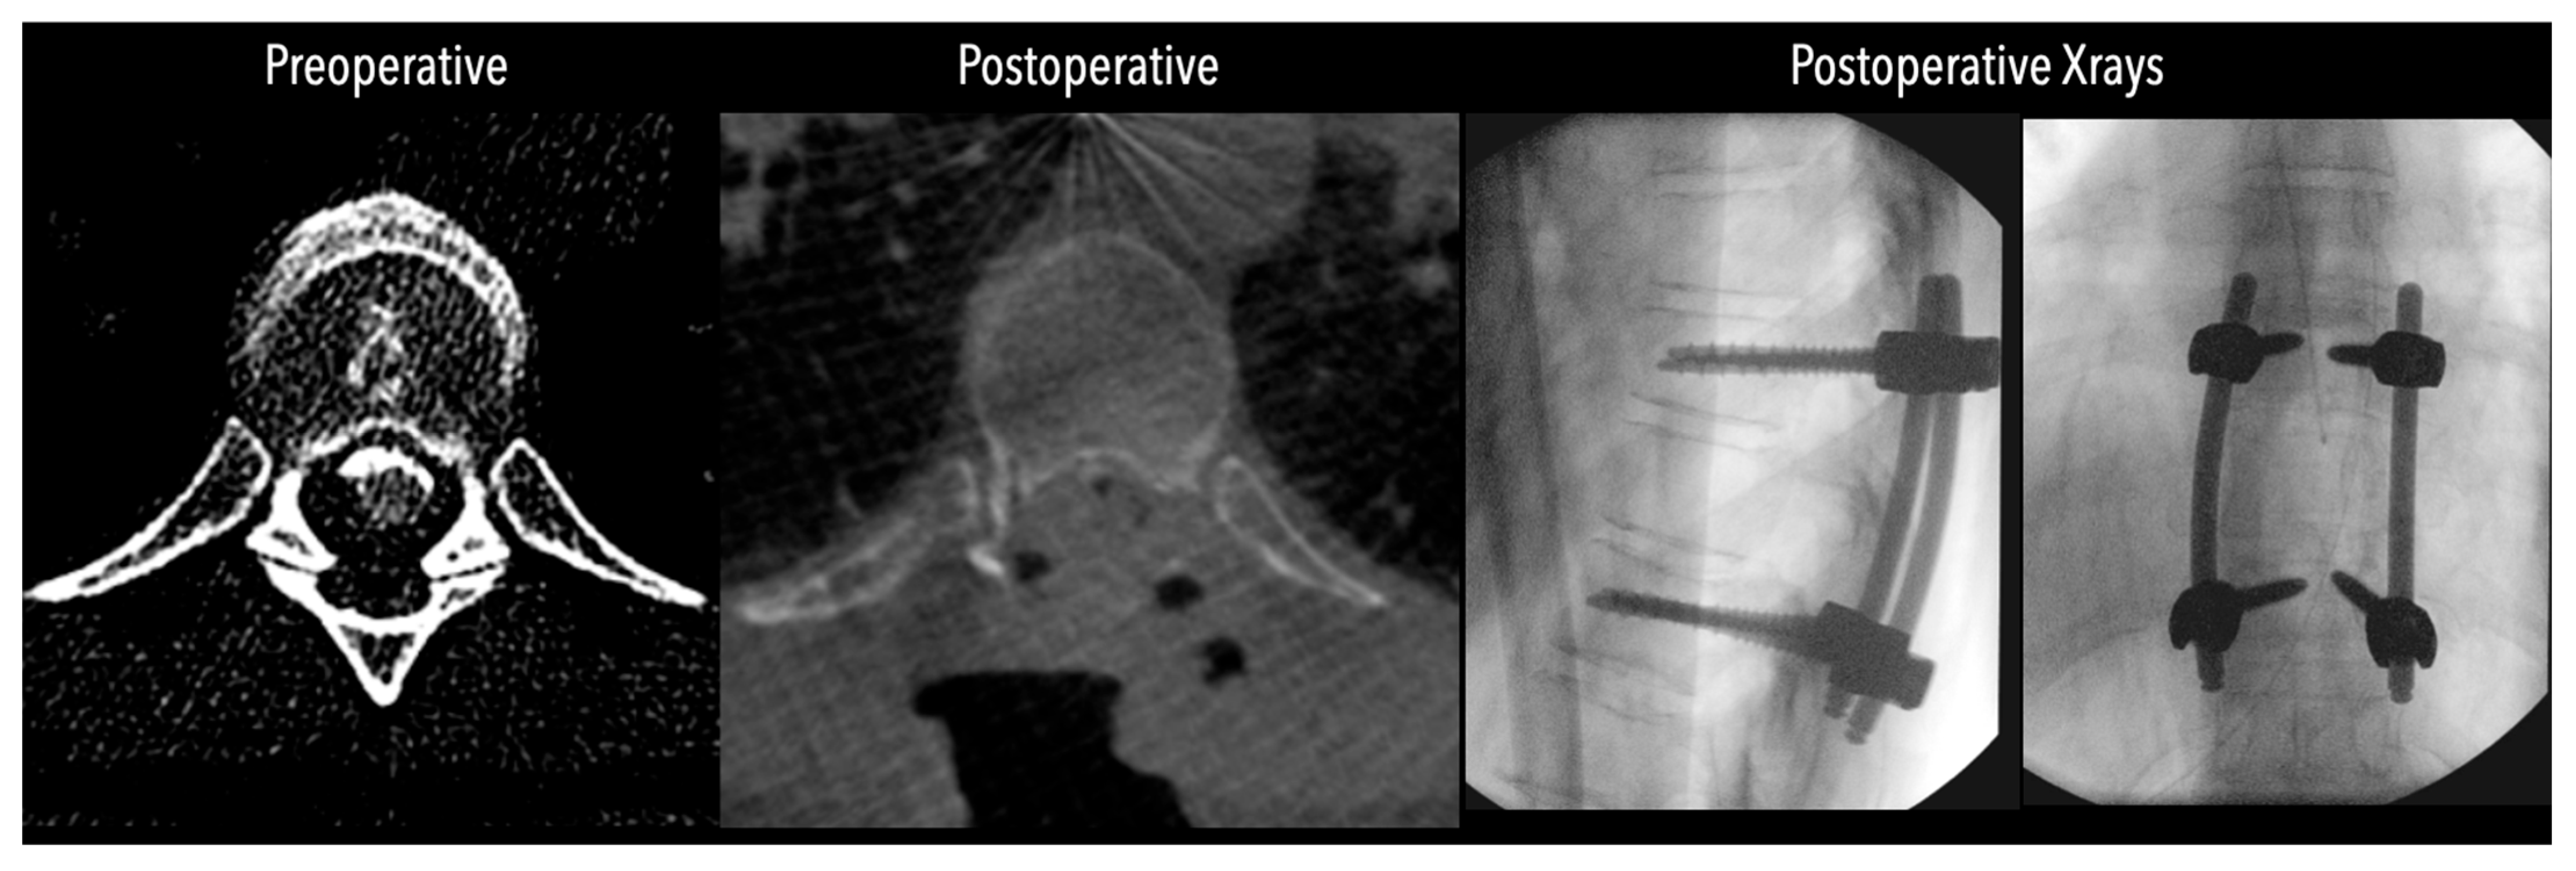

Figure 5. Left side: Comparative pre- and postoperative CT scan of a patient, illustrating complete discectomy. Right side: Postoperative X-rays illustrating fixation.

In three of the seven cases, the exiting nerve root at the level of the herniation was ligated due to poor visualization and transected extradurally to improve access. In the remaining four patients, the nerve root was either preserved or dissected intradurally using isocool bipolar diathermy and microsurgical scissors. With gentle medial retraction of the cord under gravity and protection using a micro-patty, the calcified disc was exposed. The ventral dura, when intact, was incised sharply and dissected from the disc surface where possible (Figure 2a,b and Figure 3). Disc removal was performed using a hockey-stick-shaped Misonix bone scalpel with constant irrigation, guided by intraoperative neuronavigation. The disc material was resected to a depth of 1–2 mm beyond the posterior vertebral wall to ensure adequate decompression. A second O-Arm spin was routinely performed following discectomy to confirm satisfactory decompression, especially given the limitations of the postoperative MRI due to the metal artefact (Figure 4, Figure 5 and Figure 6).